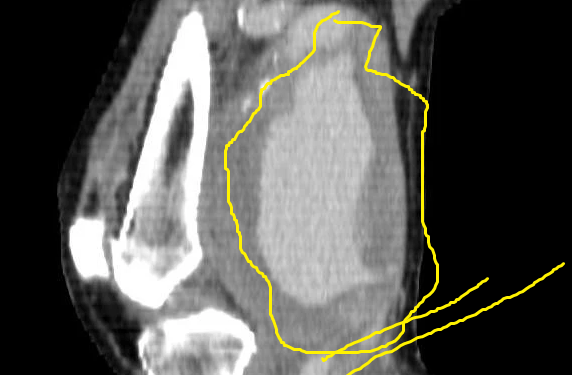

- Popliteal anevrizma, diz arkasındaki asemptomatik pulsatil kitlenin neden var olduğunu araştırırken aydınlatılır veya çoğunlukla rastgele saptanır, başka bir klinik tanı için tetkik istersin ve bir anda karşına çıkar.

- Popliteal anevrizma tromboz/rüptüre olursa ileri miktarda ektremite iskemisi görülür ki bu durum amputasyonla sonuçlanabilir.